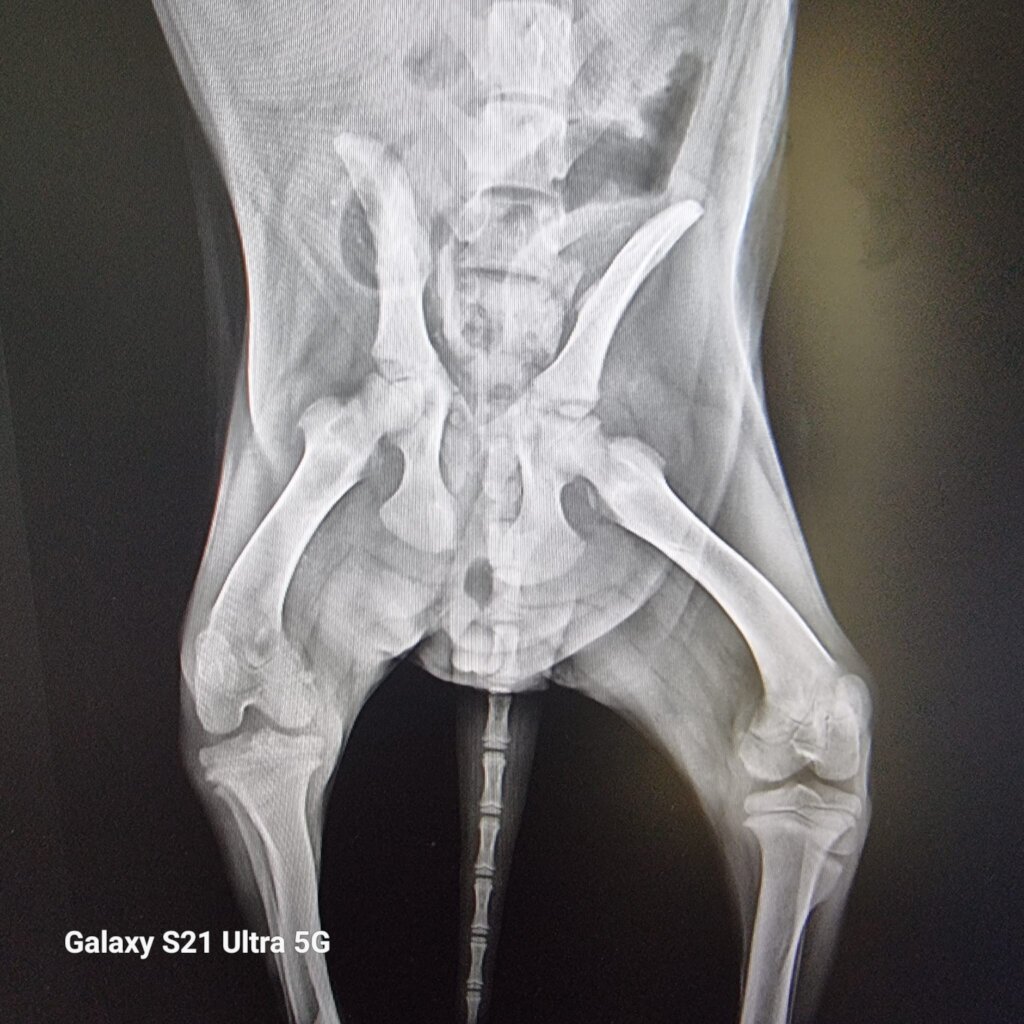

Homeless Animal Hospital, located in Piteasca, a small town near Bucharest, offers animals orthopedic services, radiography, surgical operations, inhalation anesthesia, days in intensive care, and this year the first social CT for animals in Romania will be inaugurated.

The dog arrived at Piteasca, and there an MRI and a CT scan were done. A cervical disc herniation was discov- ered. He had surgery, and after a week, the puppy was up as if he never had a problem.